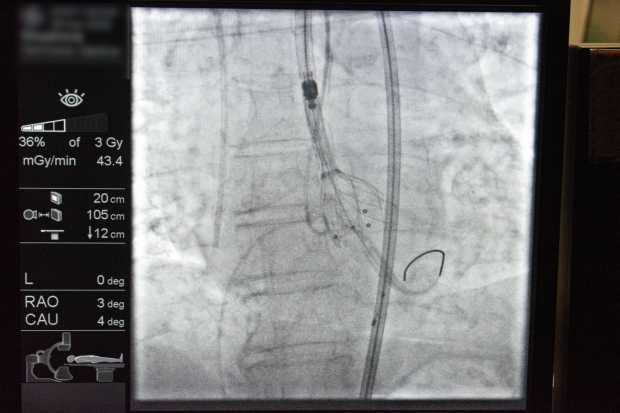

- Първата беше транскатетърно имплантиране на аортна клапа (TAVI) при пациент с високостепенна аортна стеноза – минималноинвазивна техника, която елиминира необходимостта от отваряне на гръдния кош и значително намалява риска от усложнения.

- Втората интервенция, представена от професора, беше орбитална атеректомия – съвременен метод за обработка на силно калцирани артериални плаки. МЕДИКА е сред утвърдените центрове в региона, които рутинно прилагат тази техника и я демонстрираха пред своите сръбски колеги, за които тя все още не е част от ежедневната практика.